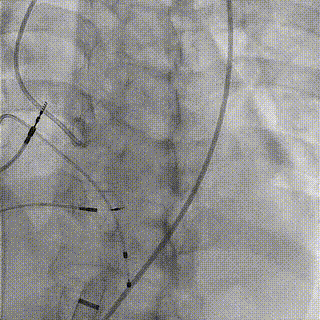

手术过程

1.LAD+LCX造影

2.右冠造影

3.主动脉根部造影

4.18mm球囊预扩

5.跨弓+跨瓣

6.释放至工作位

7.完全释放

8.术后造影,冠脉血流通畅

瓣膜释放后,复查左室-主动脉瓣峰值压差0-1mmHg,食道超声及造影像均提示瓣膜无反流,冠脉血流通畅。